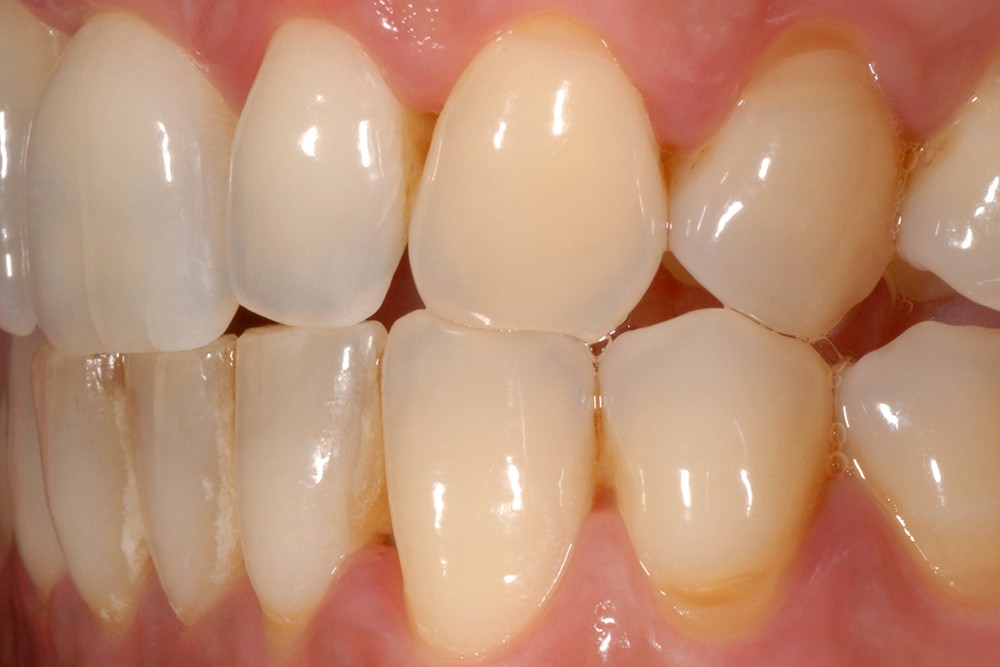

L’érosion survient lorsqu’une attaque chimique (solution acide, chélatant) rompt les liaisons intermoléculaires des tissus dentaires, potentialisant les différents autres modes d’usure mécanique (attrition, abrasion, abfraction) (fig. 5). L’aspect clinique des lésions érosives est polymorphe, mais, d’une manière générale, les surfaces sont lisses, en forme de cupules sur les sommets cuspidiens (fig. 6), de couleur satinée à terne. Les restaurations non affectées par l’environnement corrosif (amalgames, composites, alliages métalliques) surplombent généralement les surfaces amélaires et dentinaires adjacentes, alors que la morphologie dentaire est affectée. Les faces vestibulaires (fig. 7) et palatines (fig. 8) peuvent également présenter des lésions plus ou moins importantes, selon l’origine et le temps d’application de la source acide qui peut être d’origine extrinsèque (sodas, aliments acides) ou intrinsèque (sucs gastriques).